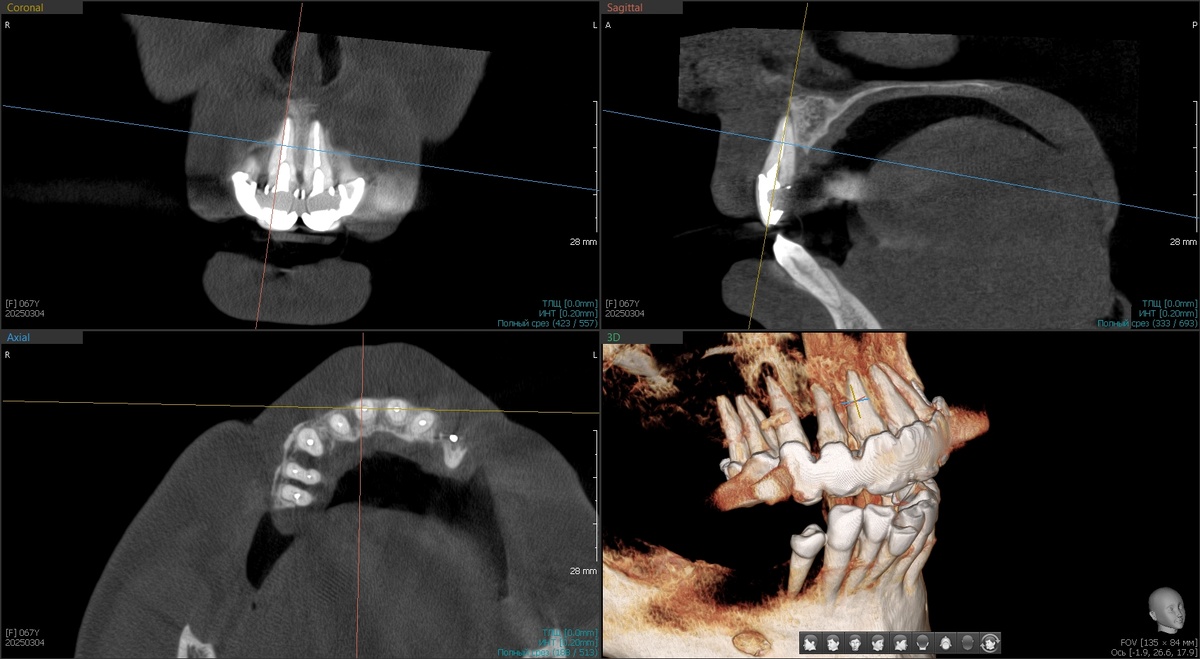

Верхняя челюсть представляла собой классический пример того, как "хорошее" лечение 20-летней давности превращается в катастрофу сегодня.

Металлокерамические коронки с нависающими краями. Под ними - гнойное отделяемое, хроническое воспаление, разрушенная кость альвеолярного отростка. Ткани постоянно воспалены, кровоточат при малейшем прикосновении.

Но это была только первая проблема. Вторая оказалась ещё серьёзнее - культевые вкладки разрушили корни зубов в пришеечных областях. Металлические штифты, установленные давно, работали как клинья, постепенно раскалывая то, что должны были укреплять.

Спасать на верхней челюсти было нечего. Только удаление и имплантация. Снизу родные фронтальные зубы остаются с пациенткой - было предложено выравнивание ортодонтическое, но в силу возраста очень просили обойтись без данной процедуры. Это чуть ухудшит протез (будет балкон, который любят бактерии), но в данном конкретном случае ситуация не патовая - такой вариант допустим.

Решили действовать планомерно. В апреле 2025 года - первый этап.

Установили 2 птеригоидных имплантата и 2 классических имплантата на нижнюю челюсть в области 4.5 и 4.6 зубов.

Что такое птеригоидные имплантаты, помните? Это специальные длинные имплантаты, которые фиксируются в крыловидном отростке клиновидной кости черепа. Эта кость плотная и, практически, не подвержена атрофии даже при длительном отсутствии зубов. Птеригоидные имплантаты позволяют избежать синус-лифтинга - наращивания кости в гайморовой пазухе.

Тотальная операция на верхней челюсти "All-on-4"

Оценили приживление апрельских имплантатов - все четыре интегрировались отлично (фото чуть ниже приложу). Можно приступать к основной работе.

1. Программа максимум - удаление всех оставшихся зубов верхней челюсти с распилом МК-моста (та ещё работёнка, стёрли несколько специальных боров в 0), установка 4 имплантатов по системе "All-on-4", отличные торки на всех имплантатах, немедленная нагрузка предвременным протезом (хлипким, он нужен для формирования контура десны для природоподобия).

2. Второй этап в тот же день - удаление зуба 4.4 на нижней челюсти, одномоментная установка имплантата, раскрытие двух апрельских имплантатов и мягкотканная пластика.

Программа максимум выполнена с апреля по сентябрь - установлено 6 имплантатов на верхней челюсти, 3 имплантата на нижней, мягкотканная пластика, предвременный протез в день операции. Всё, что планировали, случилось без эксцессов. Птеригоидные имплантаты прижились идеально, основная операция прошла без осложнений.